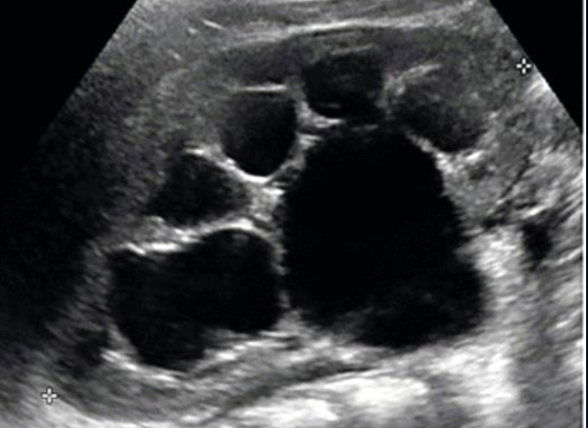

What is this?

Moderate Hydronephrosis (As it is one coherent structure there is not segmented Echogenic Structures)